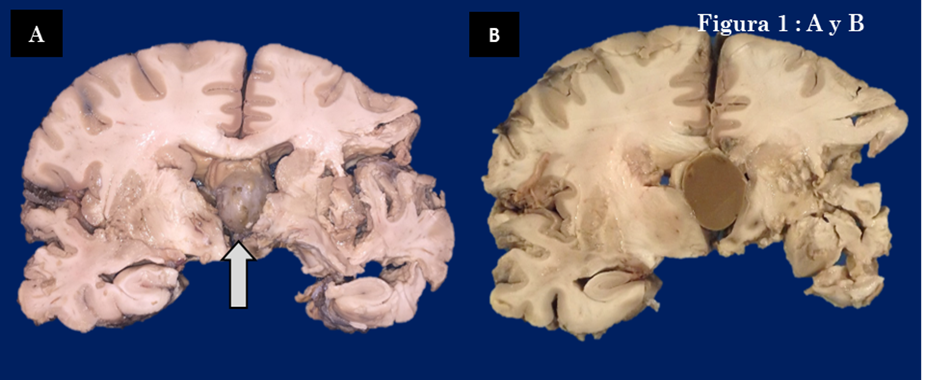

Introducción: Los quistes coloides del tercer ventrículo son raros, la evaluación forense debe determinar su relación con el mecanismo de muerte1. Descripción del caso: Mujer de 30 años, diabética, que ingresó por deterioro neurológico y falleció cinco días después, se le realizó autopsia. Hallazgos relevantes: Los cortes coronales del cerebro muestran edema severo, obliteración ventricular y datos de muerte cerebral. En el tercer ventrículo había lesión ovoide de 2.5 x 2.5 x 2cm, con superficie lisa, café claro (Fig. 1-A, marcada con flecha).

Al corte, la lesión era quística con material mucoso café obscuro (Fig. 1-B). Microscópicamente, estaba revestida de epitelio cúbico (Fig. 2-A). La pared tenía rotura evidenciada por inflamación crónica y cristales de colesterol. El contenido era material eosinófilo, granular, mezclado con eritrocitos (Fig. 2-B).